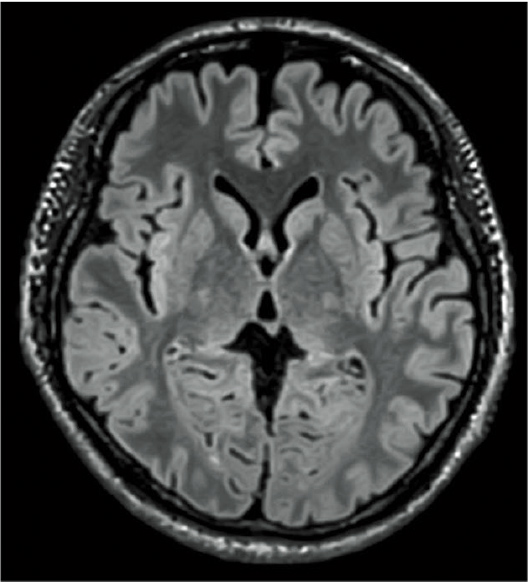

RADAR’ın TOF MRA ve GrE T2*WI’deki etkileri

RADAR, yüksek hassasiyetli sinyal düzeltme teknolojisi kullanılarak GrE sekanslarına uygulanmıştır. Bu, rutin baş incelemelerinde gerekli tüm sekanslar için RADAR’ın kombine kullanımını mümkün kılmıştır.